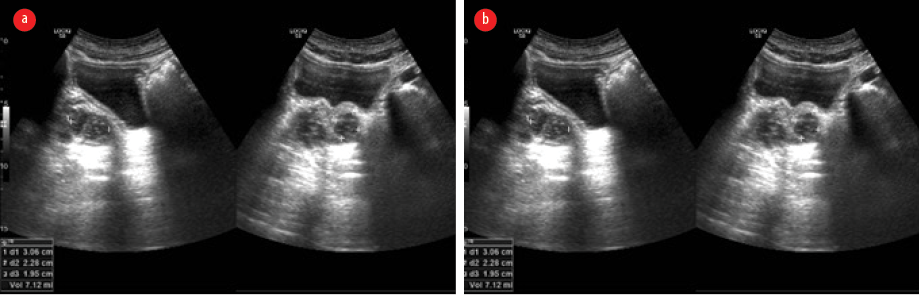

Two months later, while continuing the eradication treatment, the patient had another relapse and presented with headache and left focal motor seizures. A repeat contrast-enhanced MRI of the brain showed findings similar to the previous one, with additional edema in the ventral aspect of the medulla (more affected on the right side), which extended to the upper cervical cord, affecting the right spinothalamic and left lateral corticospinal tracts [Figure 4].

Figure 4: Repeated contrast-enhanced MRI after the second relapse. (a) Axial T2 fluid attenuated inversion recovery image. (b) Sagittal T2-weighted image shows new-onset hyperintensity involving the ventral aspect of pons and medulla.